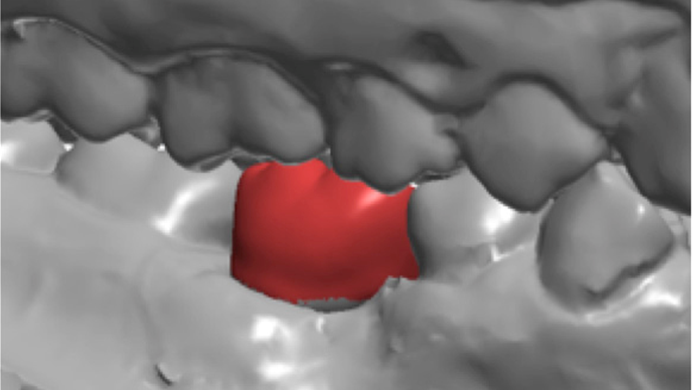

Clinical case: # 46 implant placement & GBR using i-Gen membrane for significant vertical resorption & mixed bone defect

AnyRidge, mandibular posterior, i-Gen, resorption, bone defect, bone regeneration, space management, #46, GBR, Dr. Iulian Filipov

AnyRidge implant system, i-Gen

“AnyRidge KnifeThread achieves excellent stability in regenerated bone & even in only 3mm bone height!”